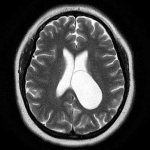

It is interesting that with conventional diagnostics using CT and MRI, no abnormalities were detected after a month, but when stimulating the cerebral cortex with short magnetic pulses, a disturbance in the processes of neuronal excitation and a longer period of inhibition than normal were detected.

- Brain MRI with angiography;

After the patient is admitted to the hospital, a comprehensive examination is prescribed to establish a diagnosis. It is based on brain tomography.

Tomography allows you to accurately determine all changes in the brain